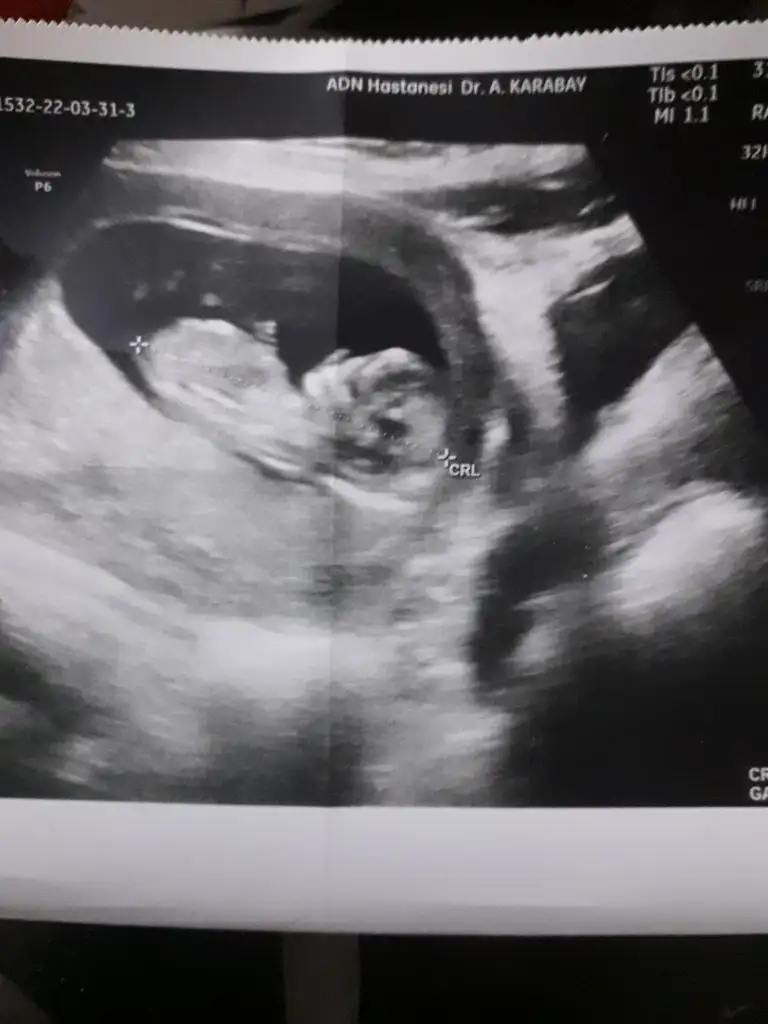

Merhabalarr, bende çook merak ediyorum ilk fotoğrafta 9+5 , ikinci de 12+1 bana da bakar mısınız rica etsemKız ve erkek görüntülerine çok bakmıştım.o yüzden tahmin edebiliyorum

Erkek yüksek bir ihtimalle canım Allah sağlıkla kucağına versin İnslalhMerhabalarr, bende çook merak ediyorum ilk fotoğrafta 9+5 , ikinci de 12+1 bana da bakar mısınız rica etsem![]()